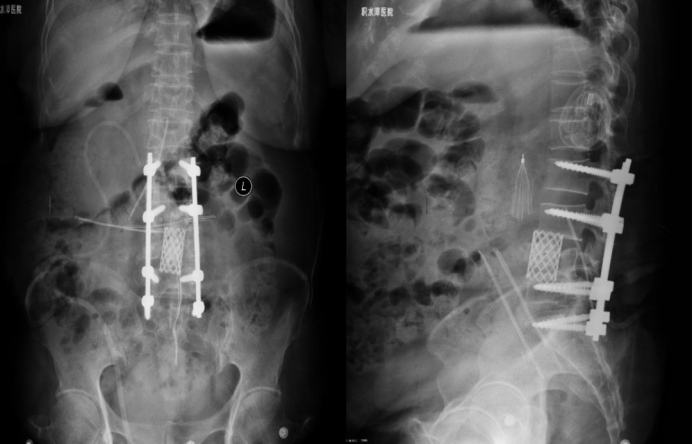

6-month postoperative imaging

6-Month Postoperative Follow-up:

6-Month Postoperative Follow-up: The position of the internal fixation hardware remains unchanged compared to the immediate postoperative status. Hyperextension angle: 17.5°; Hyperflexion angle: 15.1°; Intervertebral angular difference: 2.4°; Intervertebral translation distance: 0 mm. The implant shows no signs of deformation, displacement, loosening, or fracture. CT scan indicates fusion. Local reaction is Grade 0. Both the patient's lumbar spine functional score and quality of life score have improved compared to preoperative levels.